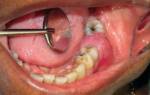

Очень неприятный запах при стоматологических воспалениях

Гнойные и воспалительные процессы в ротовой полости могут быть причиной неприятного запаха. Источниками токсинов и вони могут быть свищи, стоматиты, абсцессы, парадонтитные «карманы» и «капюшоны», а также гниющие корни старых обломанных зубов. Лечение этих воспалительных заболеваний не только поможет избавиться от неприятного запаха, но и остановит выделение токсических веществ из инфицированной области. Вот некоторые стоматологические воспалительные заболевания, которые могут вызывать неприятный запах:

- Свищевые образования — образуются для вывода гноя из десны. Например, если корни зуба инфицированы и развивается гнойный абсцесс. Один из возможных исходов — образование свища для выхода гноя в ротовую полость.